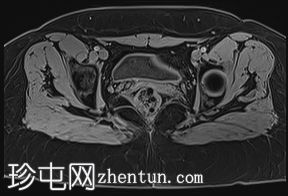

轴位

STIR序列

卵巢卵泡形态正常,可见多个小卵泡,主要位于卵巢周边,无优势卵泡。未见实性或囊性肿块。

膀胱MRI表现正常。

未见盆腔软组织肿块或淋巴结肿大。

未见明显盆腔游离积液。